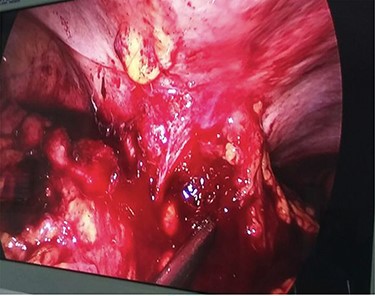

During laparoscopy, a right-sided colonic mass adherent to the lateral abdominal wall with infiltration of the subcutaneous tissue by the tumor was noted (Fig. 3).

Ascending colonic cancer complicated by an anterior abdominal wall abscess was diagnosed. Exploratory laparotomy was performed and a right colonic mass ~9 × 8 cm in diameter was found, which was widely adherent to the lateral abdominal wall, with extension through a fistulous track into the subcutaneous tissue (Fig. 4). There was no distant metastasis. Extended right hemicolectomy and lymph node dissection was performed with limited resection (en bloc) of the involved part of the lateral abdominal wall using a closure technique.

Diagnostic laparoscopy showing ascending colon adherent to anterior abdominal wall.